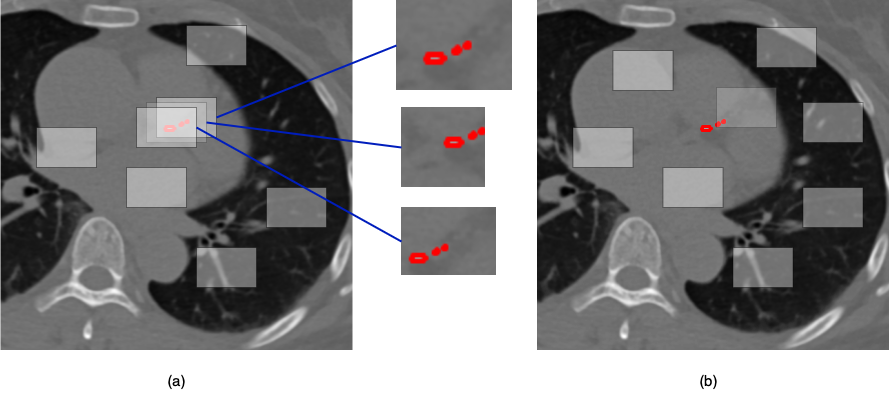

This technique uses the same number of local crops as the standard approach. In addition to these random crops, it checks for corresponding labels for the input images. These labels are used to *force* the model to learn specific local features by generating additional crops centered on annotated regions. This is depicted in Figure 6. These label-guided crops also have the medical augmentation techniques from Table 3 applied to them. By randomly selecting pixel coordinates from labels as "focusing centers," the model is guided to focus on specific regions, preventing it from learning unnecessary local features.

Refer to caption

Figure 6: Representation for label guided augmentation, focusing on specific ROIs and generating more than one cropping for calcified regions (a). Completely random local image cropping is utilized by standard DINO training (b).